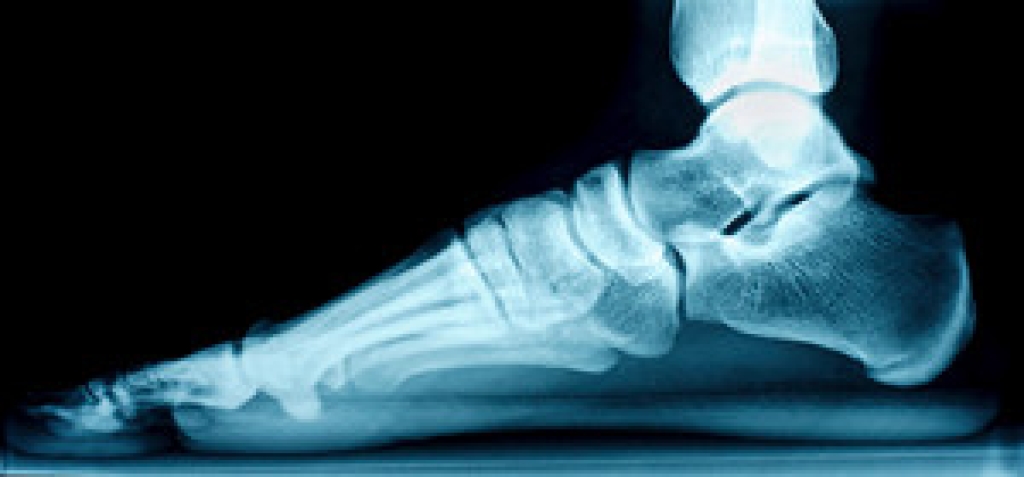

The majority of foot conditions are common and can be treated by a podiatrist. Standard diagnostic procedures are generally used to identify specific conditions and treatment can be rendered. A podiatrist also treats rare foot conditions which can be difficult to diagnose and may need extra attention and care.

Freiberg’s disease - This can be seen as a deterioration and flattening of a metatarsal bone that exists in the ball of the foot. It typically affects pre-teen and teenage girls, but can affect anyone at any age. Symptoms that can accompany this can be swelling, stiffness, and the patient may limp.

Kohler’s disease - This often targets the bone in the arch of the foot and affects younger boys. It can lead to an interruption of the blood supply which ultimately can lead to bone deterioration. The patient may limp or experience tenderness, swelling, and redness.

Maffucci syndrome - This affects the long bones in a child’s foot leading to the development of abnormal bone lesions. They are benign growths and typically develop in early childhood and the bones may be susceptible to breaking.